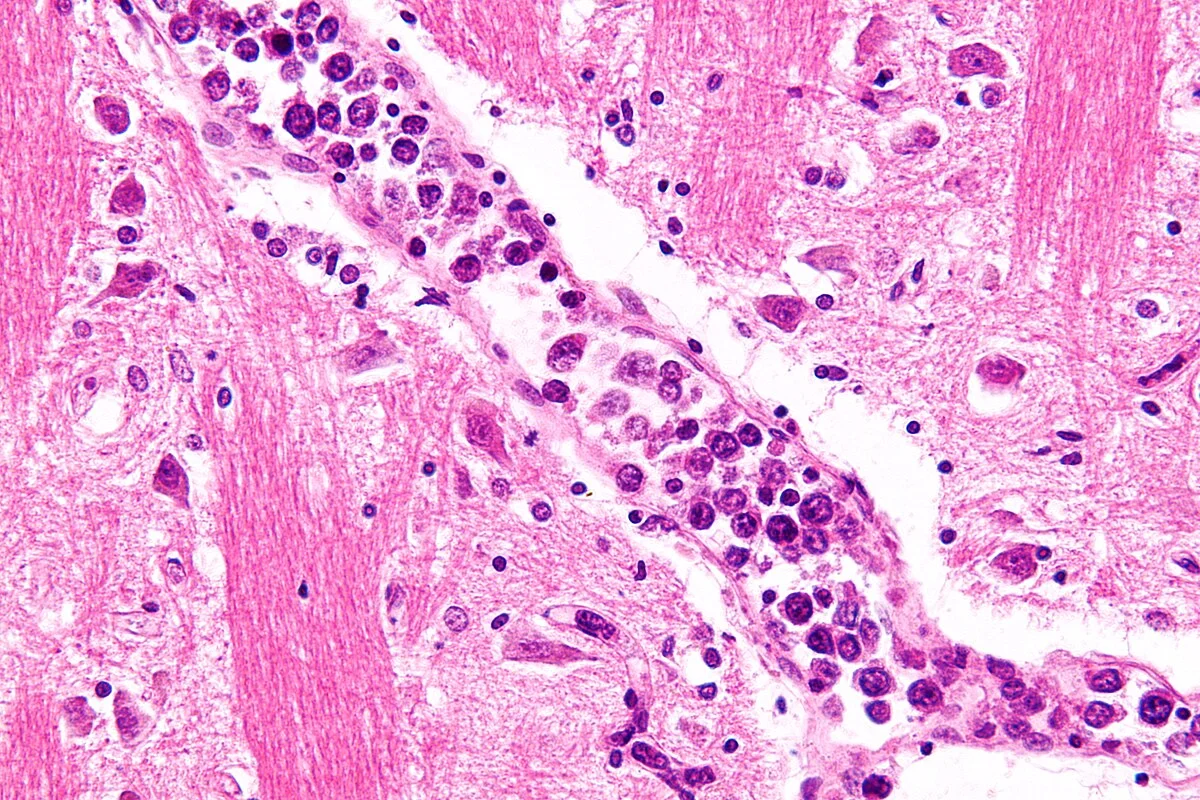

The definitive diagnosis of lymphoma relies entirely on tissue analysis. While imaging and blood tests provide crucial clues, they cannot confirm the disease. The gold standard procedure is an excisional lymph node biopsy. In this surgical procedure, an entire enlarged lymph node is removed for examination. This is superior to Fine Needle Aspiration (FNA) or core needle biopsy, which takes only small samples. The architecture of the lymph node is vital for diagnosis. Pathologists need to see not just the individual cells, but how they are arranged within the node. Are the cells growing in follicular clusters (suggesting Follicular Lymphoma) or in diffuse sheets (suggesting Diffuse Large B Cell Lymphoma)? Are the malignant cells disrupting the typical structure of the node? This architectural context is often lost in needle biopsies, potentially leading to misdiagnosis or an inability to subtype the lymphoma accurately. During the biopsy, the removed tissue is processed immediately. Fresh tissue may be sent for flow cytometry and genetic testing, while other sections are fixed and stained. If the lymph node is deep within the chest or abdomen, a surgical excisional biopsy might be too invasive. In these cases, a core needle biopsy guided by CT or ultrasound is used, obtaining multiple large cores to get as much tissue architecture as possible, though excision remains preferred whenever feasible. Excisional biopsy removes the entire node and is the diagnostic standard. Fine-needle aspiration is generally insufficient for diagnosing lymphoma. Nodal architecture distinguishes follicular from diffuse subtypes. Sufficient tissue volume is required for molecular and genetic testing. Core biopsies are an alternative only when excision is not safe.

Once tissue is obtained, the pathologist uses advanced techniques to identify the specific cell lineage. Since B cells and T cells look very similar under a standard microscope, molecular tagging is required. Immunohistochemistry (IHC) involves applying antibodies to the tissue slide that are tagged with a color. These antibodies bind to specific proteins (antigens) on the surface of the cells.

For example, CD20 is a protein found on the surface of most B cells. If the tumor cells stain positive for CD20, the diagnosis is narrowed to a B-cell lymphoma. CD3 is a marker for T cells. CD30 and CD15 are classic markers found on the Reed-Sternberg cells of Hodgkin Lymphoma. This “protein fingerprinting” is essential for correct classification.